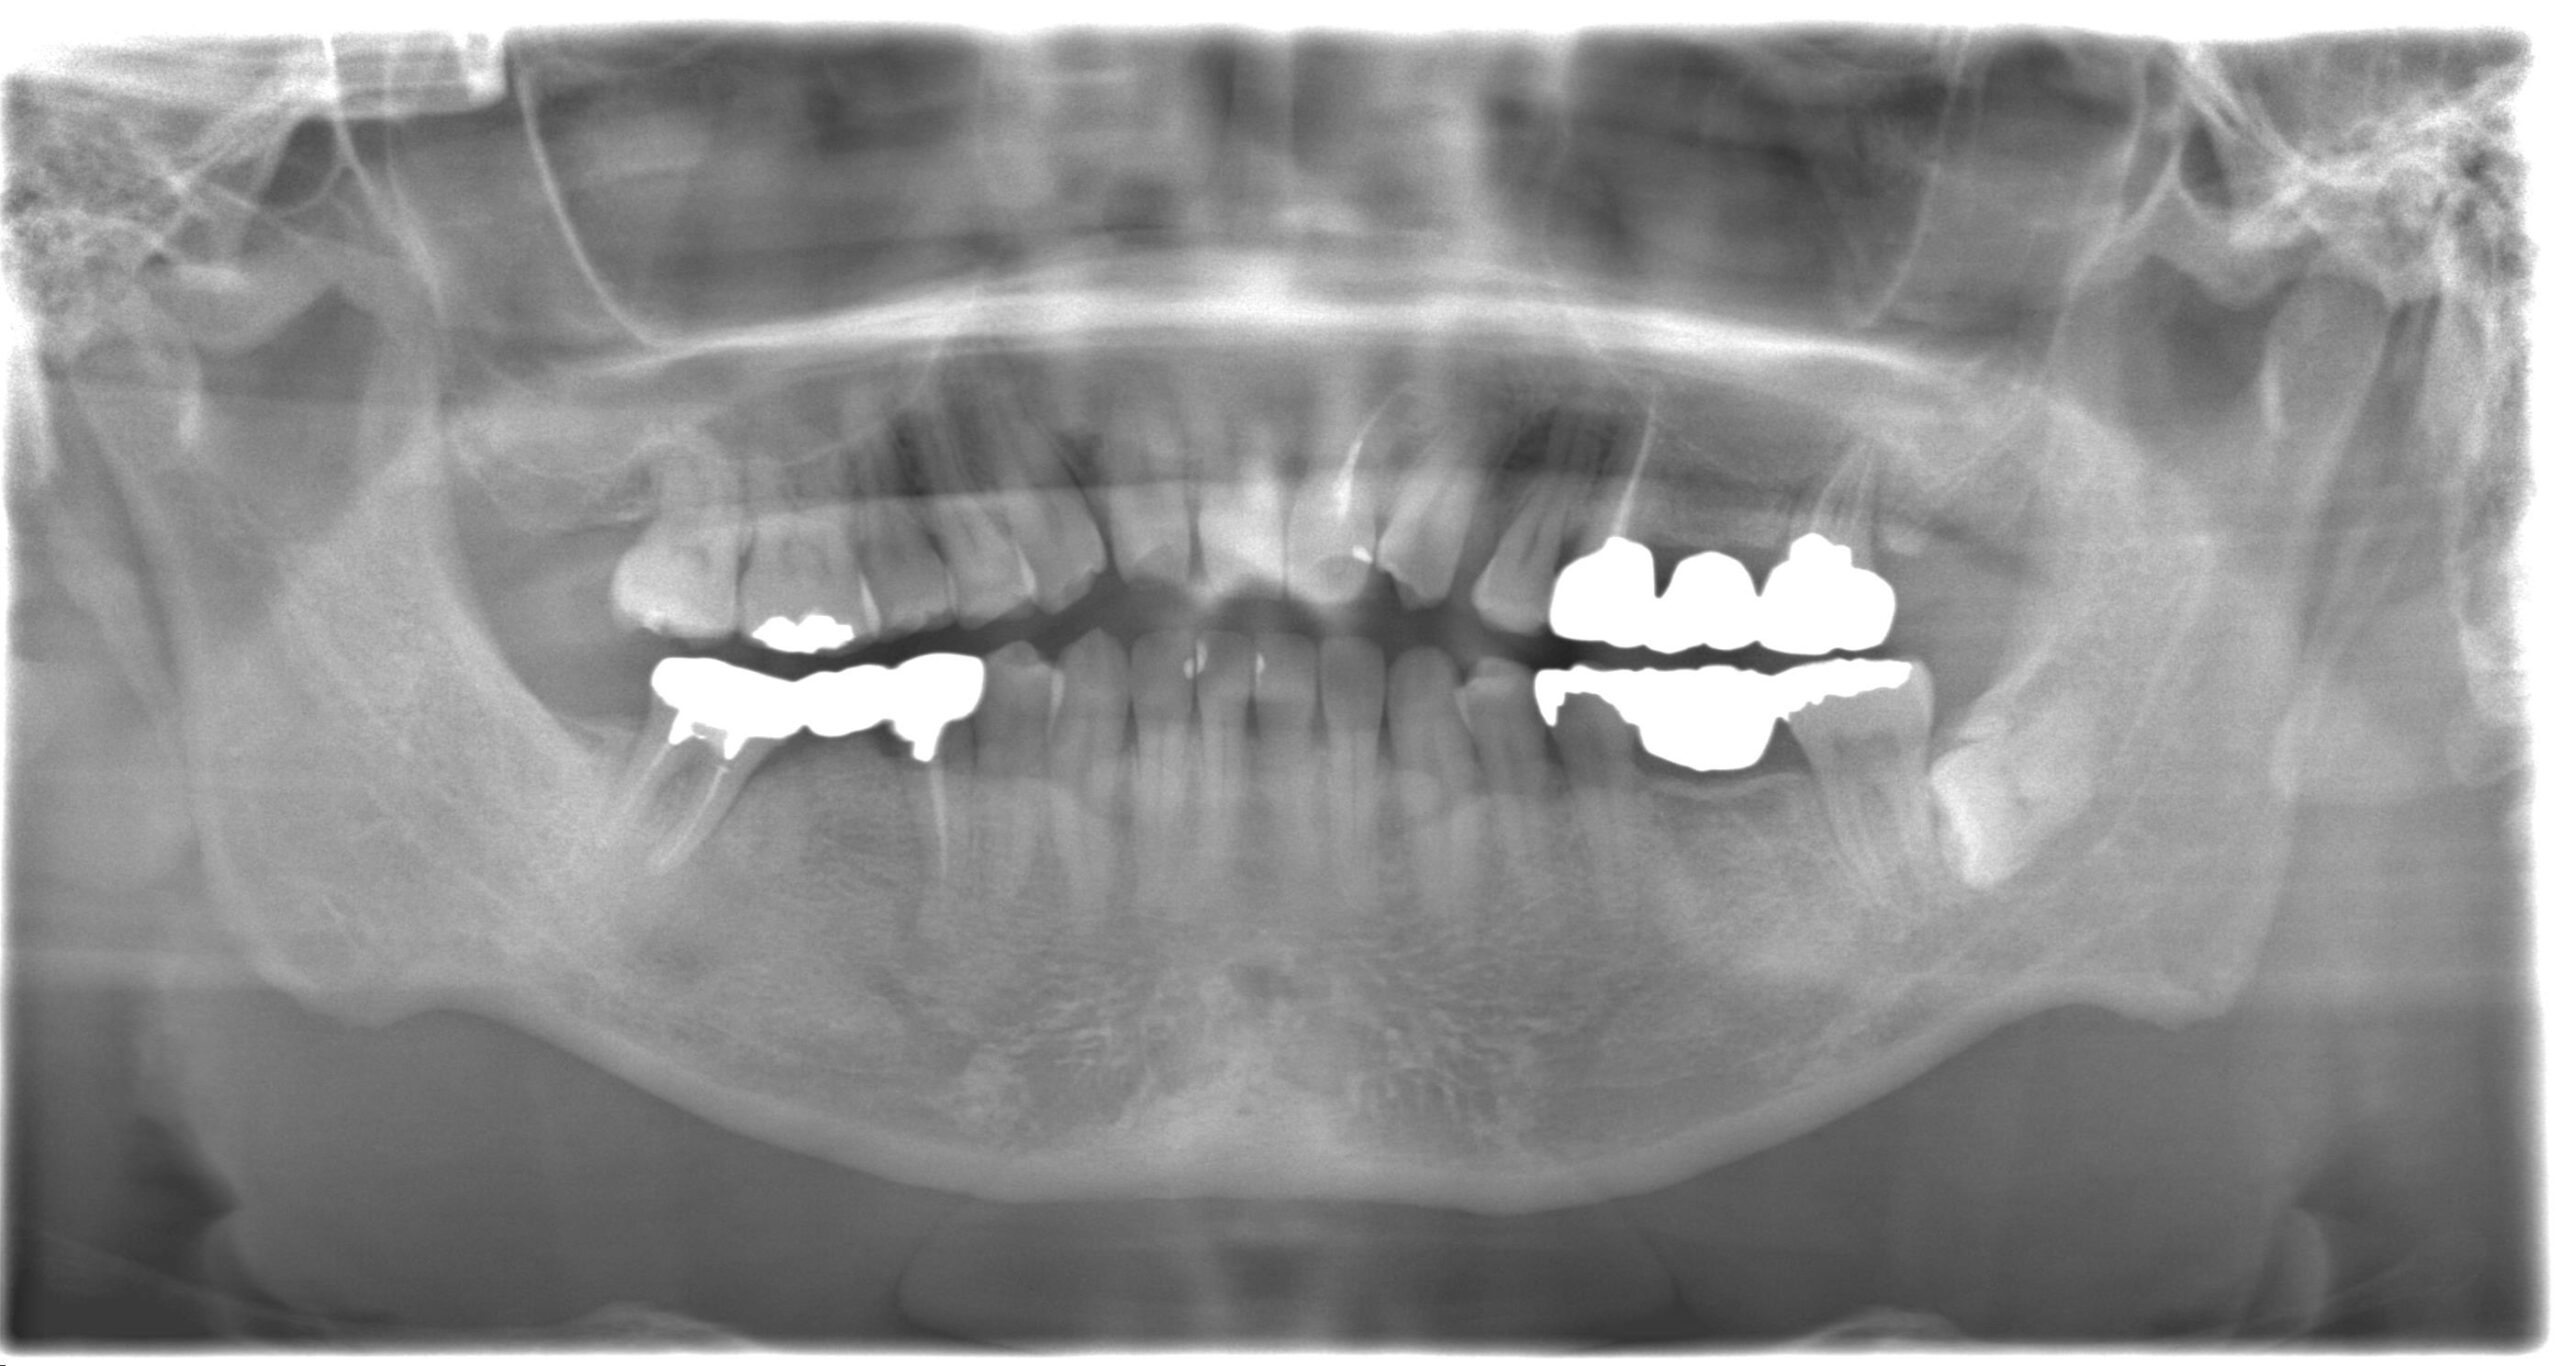

レントゲン、口腔内写真

- パノラマレントゲン撮影

ではご説明しますね。こちらのレントゲン写真を見ていただくと左の前歯に白い線が一本入っていると思います。こちらは神経を処置した後の根充材というものが入っているんですが、根の治療が不充分に思えます。まず根の治療を綺麗にやり直し、その上にファイバーコアという土台を立て、その上にセラミッククラウンを被せるというやり方で治していきます。セラミッククラウンを作る時は両サイドの歯と完全一致するようにシェードテイキング行っていきます。